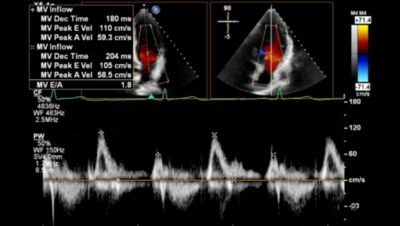

AI apps run in the background during image capture to identify images based on a selected application such as Strain.

Fully automated 2D doppler, length and strain measurements.

AI-driven automated measurements, from AI features such as Auto Measure and AutoStrain, reduce the number of keystrokes and clicks6, potentially alleviating the physical burden on clinical sonographers.